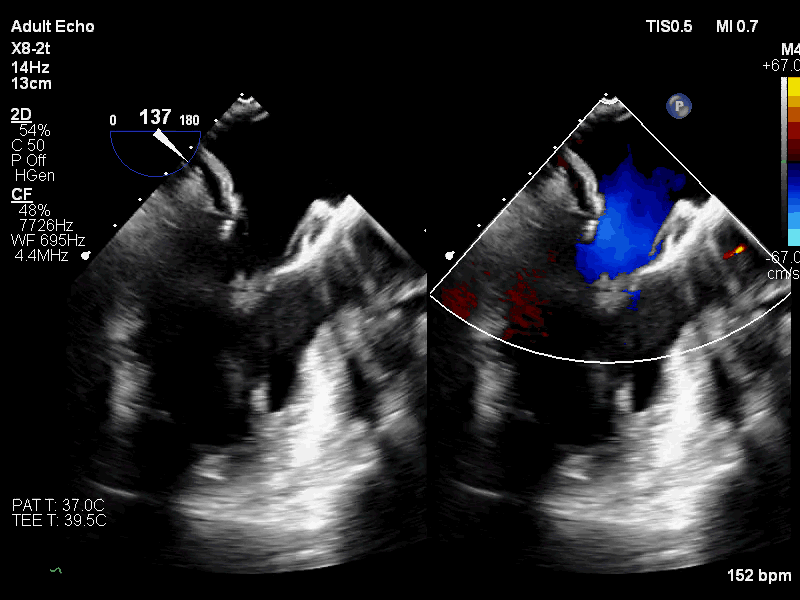

手术患者为一位高龄女性,多年来有间断发作的活动后心慌症状,近1年来患者胸闷气喘日益加重,呼吸困难,严重影响日常生活,于12月21日到武汉协和医院就诊,超声心动图检查显示二尖瓣口收缩期左房侧见大量反流信号;二尖瓣重度关闭不全;左心增大;左室收缩功能测值临界;心律失常。经武汉协和医院专家团队进行深入分析,反复讨论后最终决定采用国产二尖瓣瓣膜系统(TruDelta®)为患者进行微创介入二尖瓣置换术。

手术采用心尖入路,术中利用TEE引导确定心肌穿刺点,穿刺后导丝顺利跨二尖瓣进入左心房;TEE引导反复确认导丝未从腱索中穿过后,沿导丝推进输送系统,开始释放瓣膜;在二维和三维超声引导下完成同轴定位、D型定位后,完全释放瓣膜,撤出输送系统;最后根据血压调整瓣膜张力,进行心尖固定。

术后即刻超声心动图评估显示二尖瓣瓣膜释放位置精准,锚定稳固,无瓣周漏和中心反流,瓣膜工作形态良好,手术取得圆满成功。